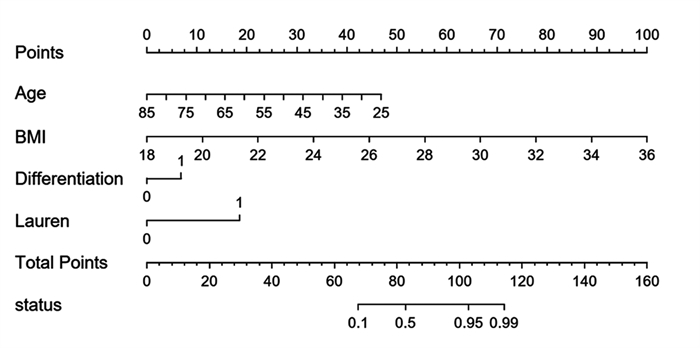

结果年龄、BMI、低分化、Lauren分型为弥漫型是胃癌术前N分期不足的独立危险因素(P < 0.05)。术前N分期不足组预后生存显著差于准确组(P=0.041)。预测模型的ROC曲线AUC为0.935,敏感度为85.9%,特异性为96.9%。

结论年龄越小、BMI越高、低分化、Lauren分型为弥漫型是术前N分期不足的独立危险因素。本研究基于年龄、BMI、分化程度、Lauren分型建立的术前N分期评估模型,具有较高的可信度。

ResultsAge, BMI, poor differentiation, and Lauren's classification as diffuse were independent risk factors for preoperative N-stage deficiency in gastric cancer (P < 0.05). Prognostic survival was significantly worse in the preoperative N stage-inadequate group than that in the accurate group (P=0.041). The AUC area was 0.935, with a sensitivity of 85.9% and specificity of 96.9%.

ConclusionYoung age, high BMI, poor differentiation, and Lauren's classification as diffuse are independent risk factors for preoperative N-stage deficiency. The established preoperative assessment model based on age, BMI, differentiation degree, and Lauren's classification in this study has relatively high credibility.